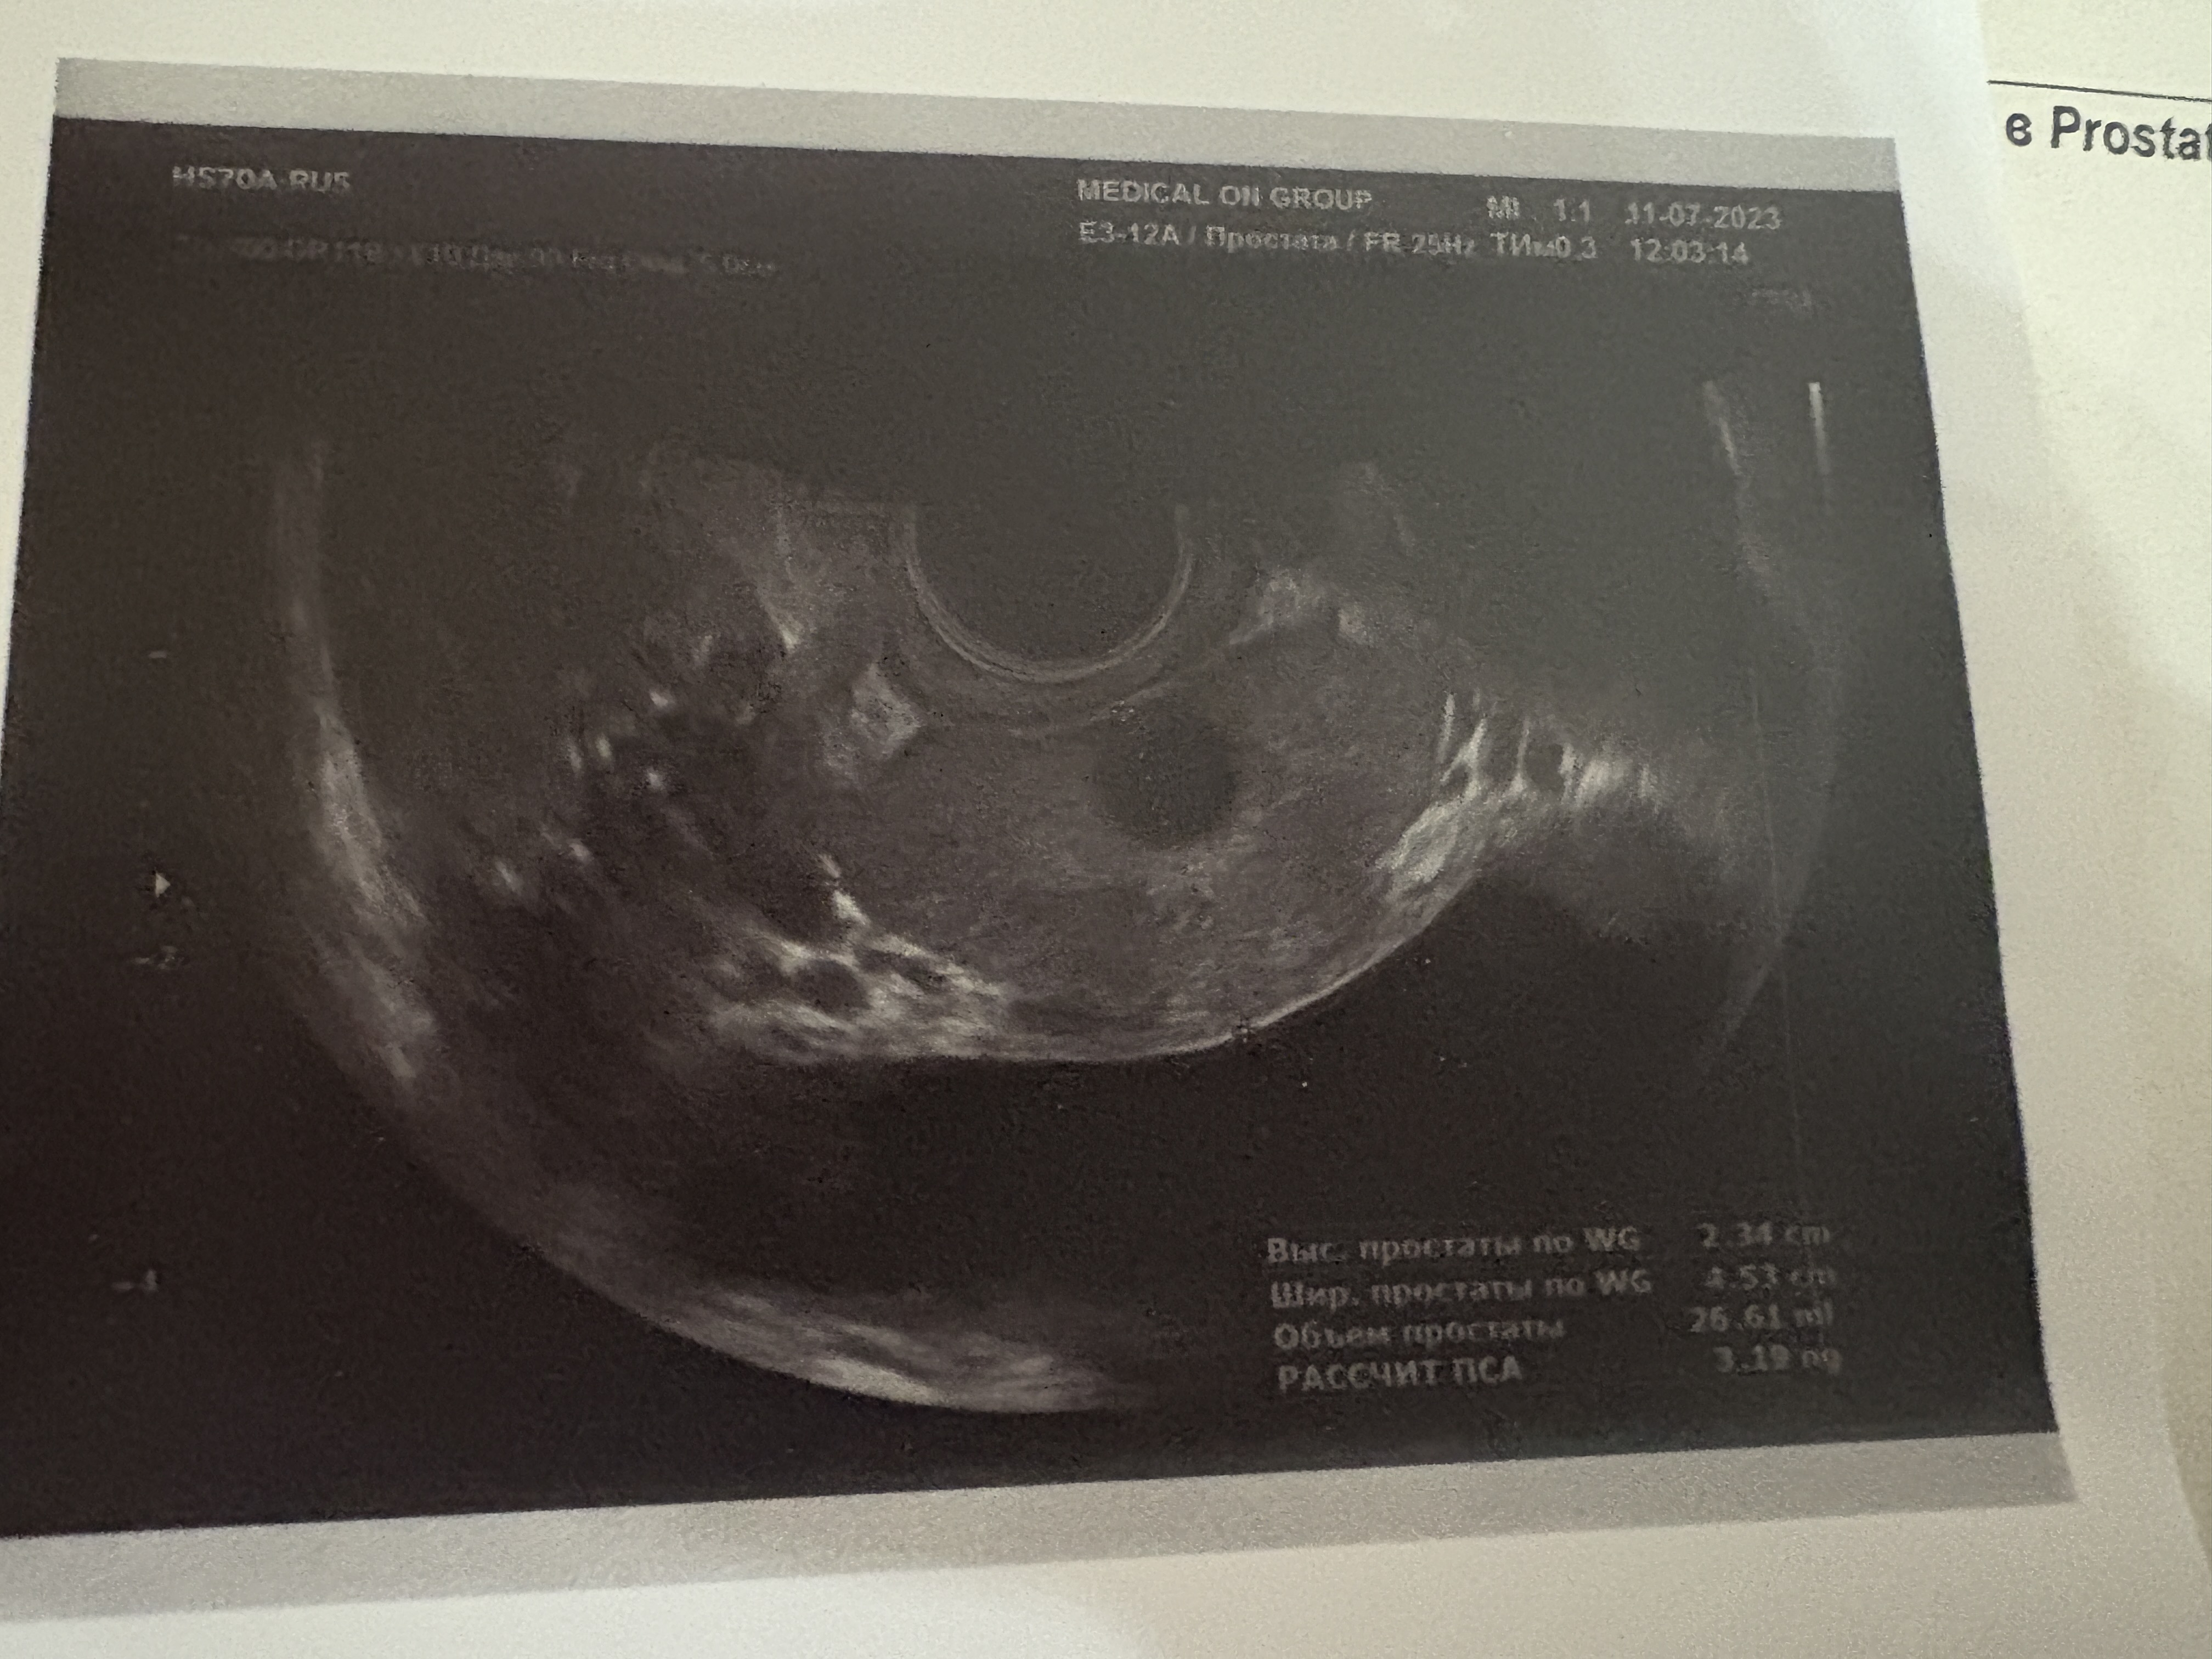

сегодня ходил делать доплерографию, ожидал что все будет ок, но оказалось что с уколом каверджекта эрекция была медленной и неполной, при том когда мастурбирую она получше так то, очень удивлен этому, я вобще думал что у меня беды с башкой, а тут врач говорит что у меня проблемы с артериями, хорошо хоть не с венами, если бы вены то это билет в один конец, хотя с артериями тож не сильно хороший случай, но тут хотя бы что то можно сделать, скорее всего дальше досдам гормоны и вместо государственного уролога пойду туда же где делал доплера

в заключении написали признаки артерогенной недостаточности писюна средней тяжести, кто нибудь сталкивался с таким? лечение помогло? я вобще бы не подумал что у меня есть какие то проблемы еслиб не решил